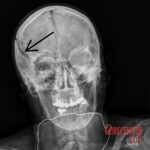

SLOVENIA – JANUARY 1, 2024 56-year-old woman from Slovenia was hit by a stray firework set off by a relative to celebrate the arrival of the year 2024. The rocket penetrated the woman’s right eye through the cranial cavity and damaged her brain. Despite immediate medical attention, she was pronounced dead.